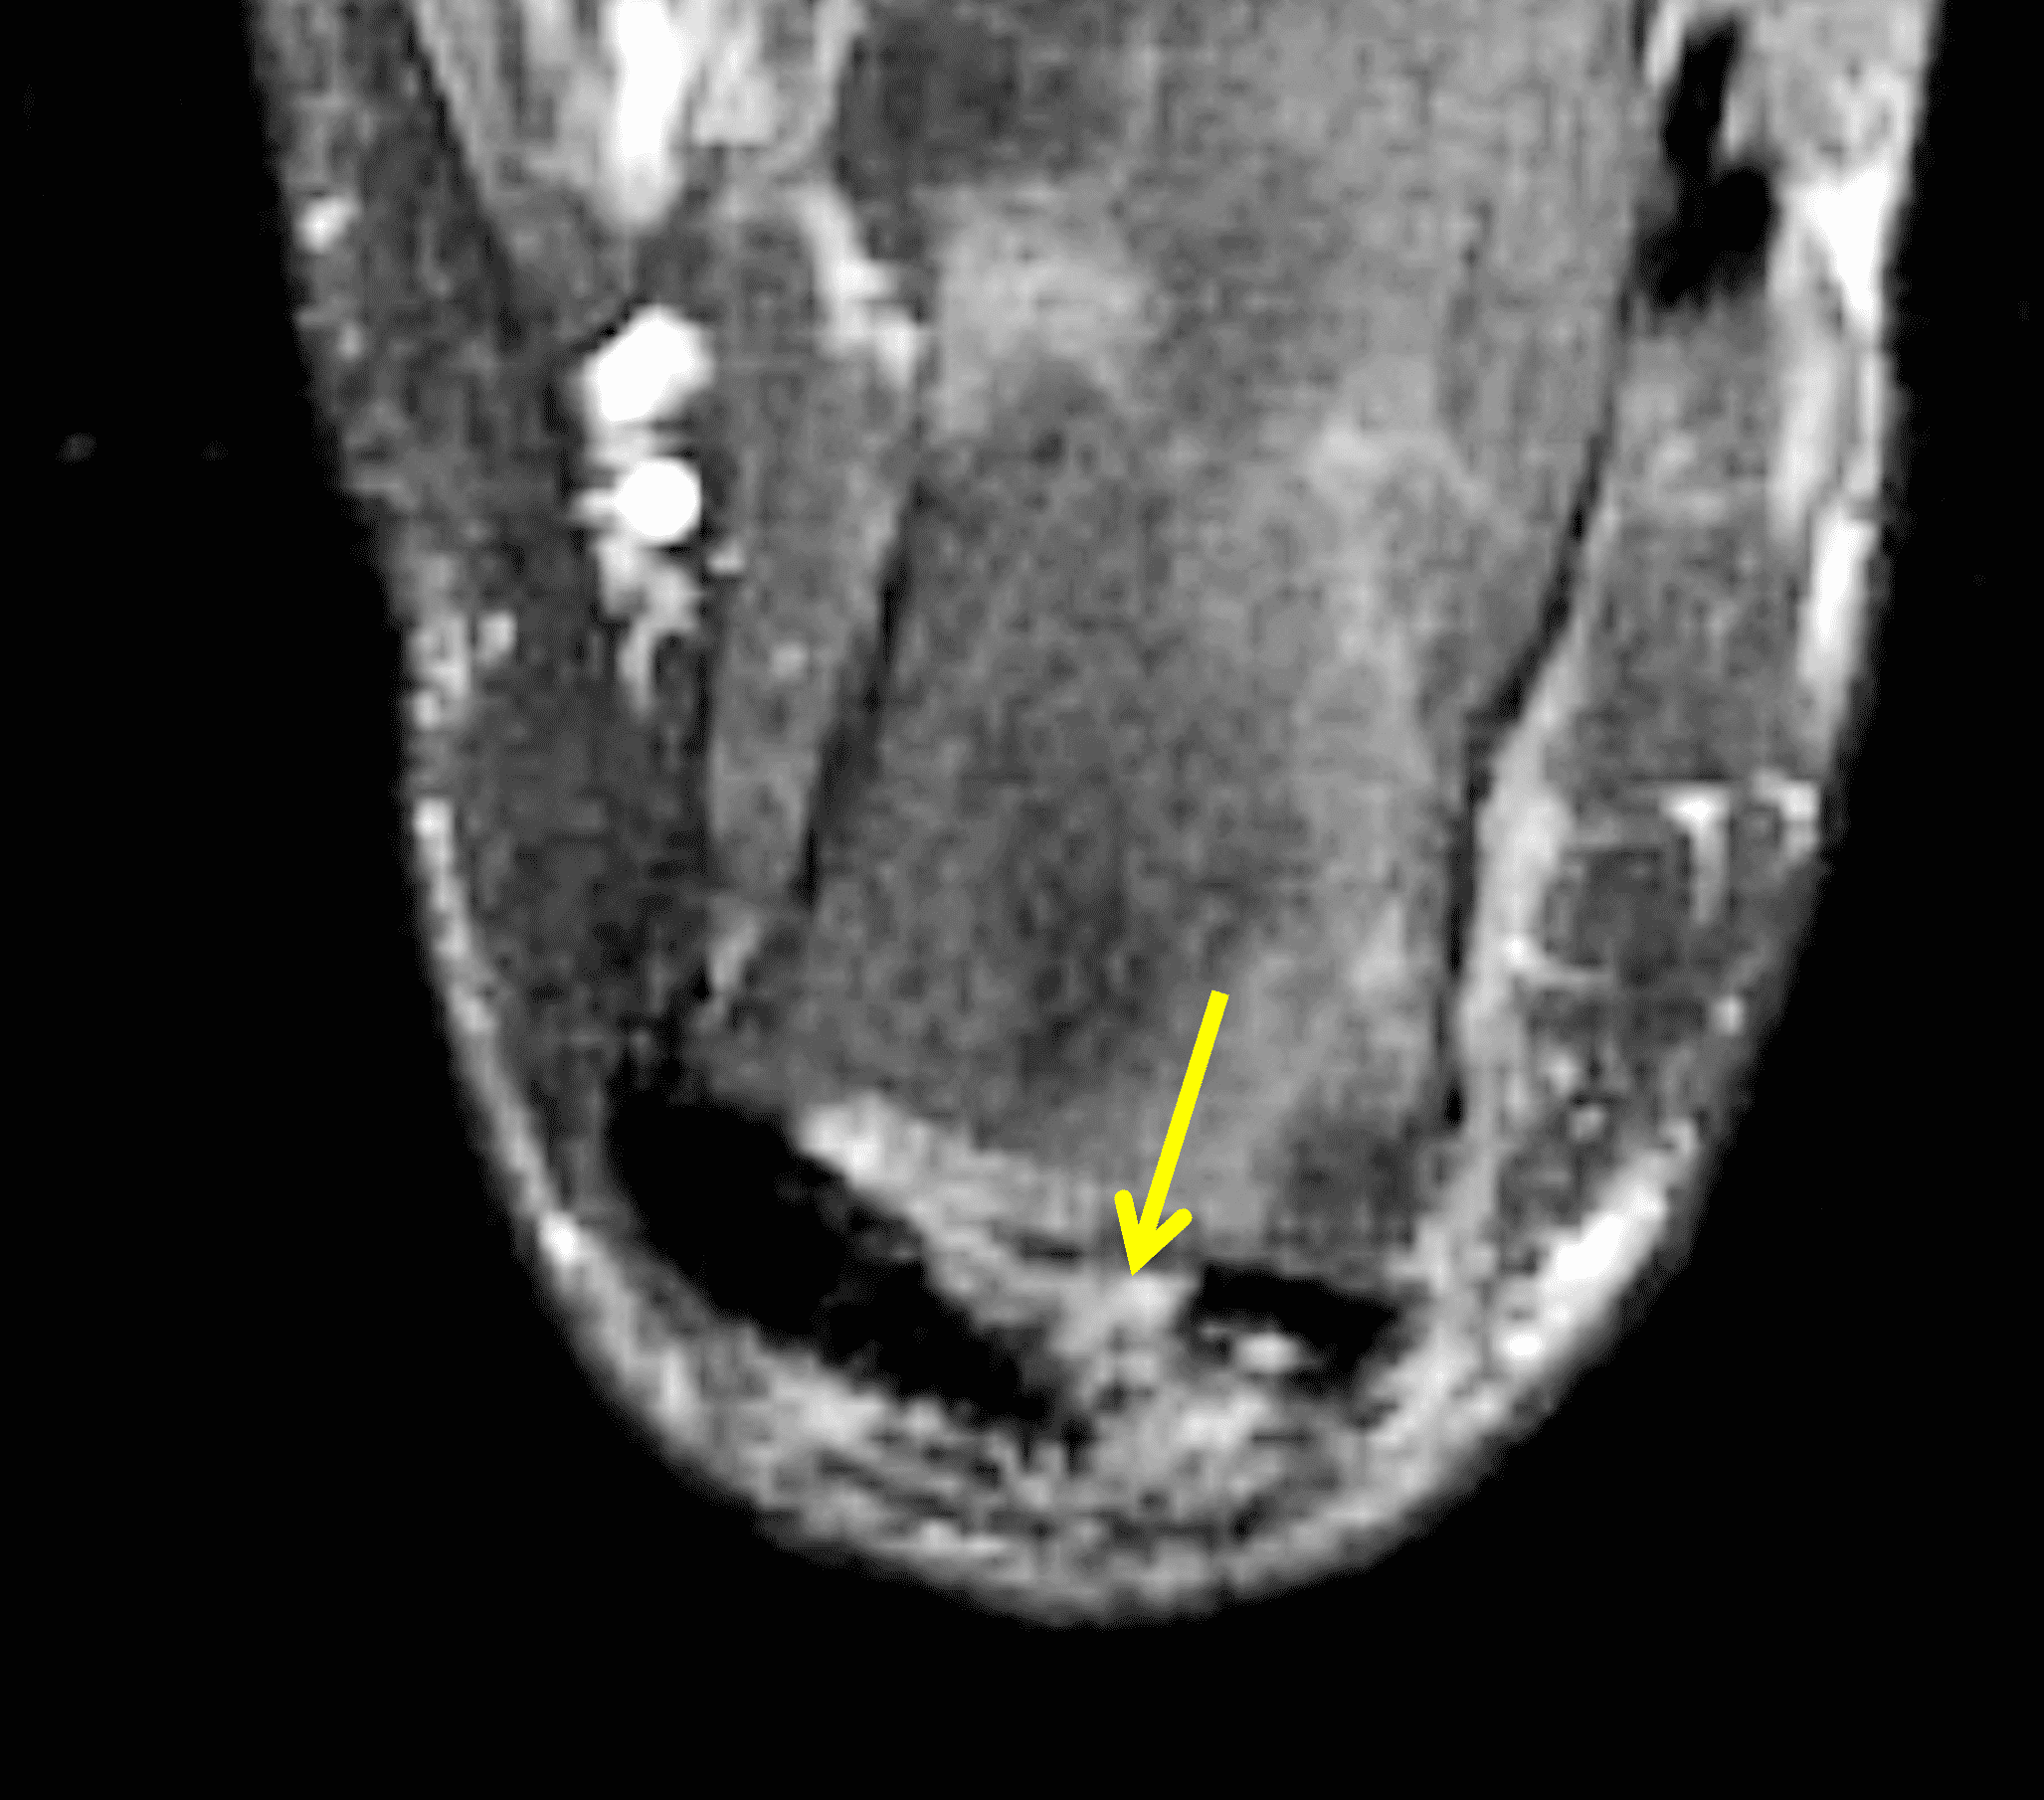

Figure 2: Complete Achilles tendon rupture. (2A) The lateral radiograph shows a thick and indistinct proximal Achilles tendon contour (arrows). (2B) A fat-suppressed T2-weighted image shows complete rupture of the tendon with a fluid-filled gap (yellow arrow) measuring 1.5 cm in length, located 10 cm cranial to the tendon insertion (blue arrow) and just distal to the edematous myotendinous junction (red arrow). The tear is superimposed on diffuse tendinosis. (2C) A sagittal T1-weighted image confirms the diffuse tendinosis. Fluid extends anteriorly into Kager’s fat pad (arrow) suggesting disruption of the anterior paratenon. (2D) A transverse fat-suppressed T2-weighted image through the proximal tendon shows no intact fibers (arrow), confirming the full-thickness rupture.